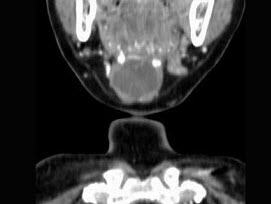

- 单项选择题女,57岁,颈部不适,CT如图所示,应诊断为()。

- C